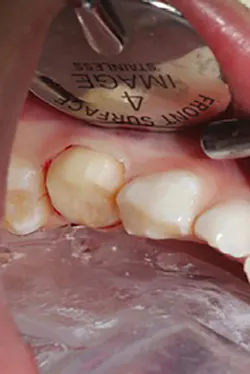

The steps for preparation and cementation were as follows. First, local anesthesia was delivered. Second, isolation was achieved with an isolation system (Isodry). Third, preparation steps were undertaken: Occlusal preparation was completed using a high-speed handpiece with copious amounts of water and a coarse, long-tapered diamond bur (NuSmile) to achieve an occlusal reduction of 1.5–2 mm. Circumferential reduction of approximately 15–20% was carried out using the same bur. In order to visualize the completeness and evenness of the preparation, a full circumferential reduction supragingivally was completed at this stage. A subgingival preparation was again completed using a high-speed handpiece with copious water and a finer, more tapered diamond bur (NuSmile). As required, a full subgingival reduction to approximately 1.5 mm depth was achieved, ensuring no ledges and a smooth featheredge margin (figure 2). It was essential that the crown fit passively and be able to be seated completely unencumbered. In order to ensure fit and occlusion and to prevent contamination of the zirconia crown to be cemented, a Try-In crown (NuSmile) was used (figure 3). Refinements to the preparation to facilitate fit and occlusion were done at this point.

Figure 3: Try-In crown (NuSmile)